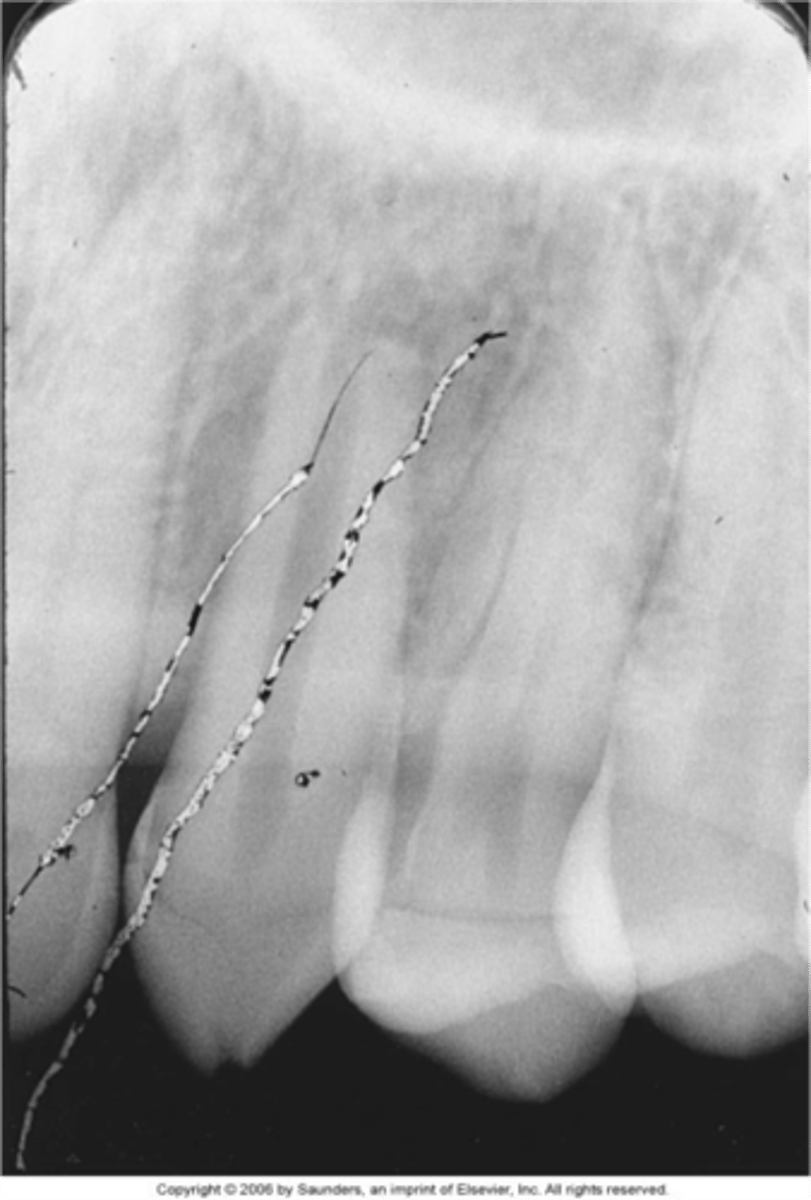

static electricity

thin, black, branching lines

<p>thin, black, branching lines</p>